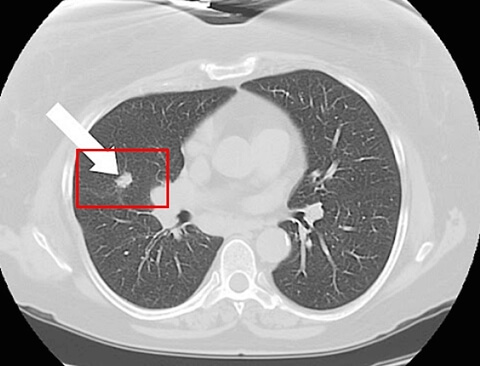

그리고 최소한은 검진이라도 국가에서 해주는 저희가 국가검진이 아주 잘 돼 있다고 하는데, 엑스레이나 저소량 시티 같은 그런 국가검진이라도 꾸준하게 이제 잘 챙겨서 잘 받으시고 어떠한 호흡기 증세가 있을 때 빨리 전문가와 만나서 필요한 검사들을 협의하시는 것이 좋을듯 동등합니다